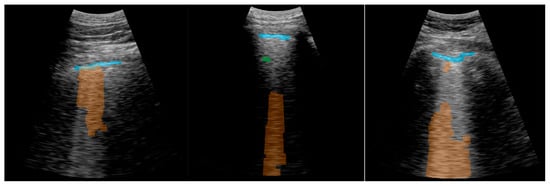

2.5.4. Visualization

3.2. Real-Time Implementation Results